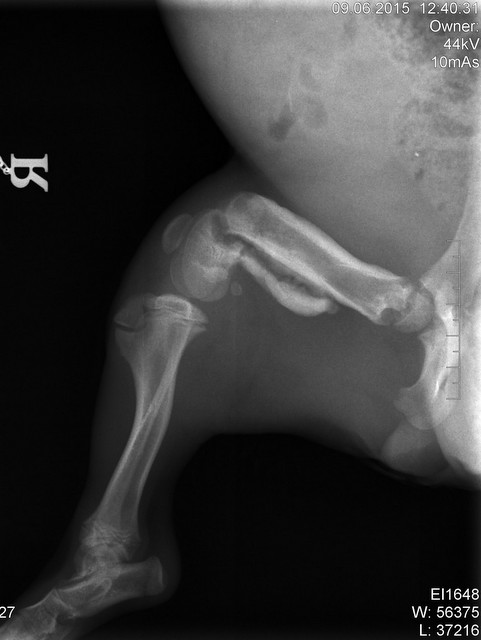

Die ebenfalls noch sehr junge TYRA - sie hat ein gebrochenes Beinchen und die rechte Hüfte ist gebrochen, das Beinchen wurde bereits auf Zypern versorgt, doch die Hüfte muss noch operiert werden. Tyra hat ihr liebevolles Zuhause zwar schon gefunden, aber wir wollen diese Operationskosten auf jeden Fall gerne übernehmen.